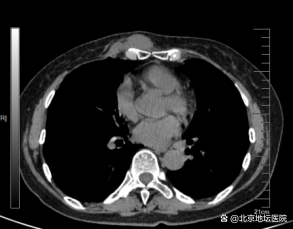

张阿姨入院后,胸外科团队尽快完善了各项术前检查。经胸部CT检查显示,复发的肿瘤位于胸骨下端右侧,与周围组织分界不清,甚至已经侵犯胸骨和临近肋骨。为了确保最好的手术效果,杨龙海副主任带领团队通过认真的术前讨论,并与麻醉科团队经过科学评估,制定了完善的手术计划。

术前检查